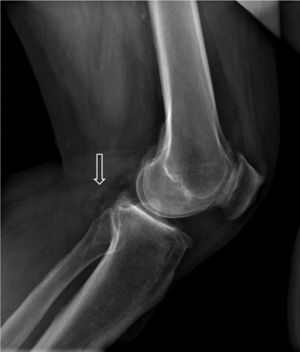

Figure 2.

CT angiogram of MMII. Axial slice. Posterior displacement of the left popliteal artery (circles).

Figure 3.

CT angiogram. Sagittal slice. Maximum intensity projection (MIP). Thrombosis of the popliteal artery (arrow) with distal rechanneling.

A male, 67 years of age, obese, with high blood pressure and dyslipidemia presented at the emergency department due to pain, cold and functional impairment of his lower left limb of 24-h onset. During anamnesis, the patient stated he had had a chronic intermittent pain in his left knee for a long time. A previous simple knee X-ray showed an osteochondroma (Fig. 1). The patient presented with a femoral pulse but with no popliteal and distal pulses. Artery examination was normal in the contralateral extremity. A CT angiogram was requested for the lower limbs which showed thrombosis of the popliteal artery adjacent to the osteochondroma (Figs. 2 and 3). We decided to perform in situ revascularization with femoro-popliteal saphenous vein graft (Fig. 4) avoiding the tunneling technique for anatomical positioning. To date, after 3 years of follow-up with eco-Doppler, the bypass continues maintaining permeability with ankle-arm index of 0.9, and no signs of popliteal vein injury.

Osteochondroma is the most common pseudotumoral bone lesion. The radiologic pathognomonic characteristic of this tumor is the cortical and medullar continuity of the lesions with the bone from which they protrude.1 They may be single or multiple.2 Some of the most common complications are the presence of bone deformity, fractures,1 vascular compromise3 and neurological compromise,4 formation of a bursa5 and malignant degeneration.6 Diagnosis may be made with an X-ray, although other imaging methods such as a scan, CT and MR may be used in suspected cases when symptoms occur or are in unusual locations.1 Vascular compromise may be caused by displacement of blood vessels (arteries and veins), by stenosis, occlusion and the formation of pseudoaneurisms, with the latter being more frequent at knee level,7 involving the popliteal artery or being presented as arterial thrombosis,8,9 as in this clinical case. Its presentation as thoracic outlet syndrome in the case of rib lesions has been described.10